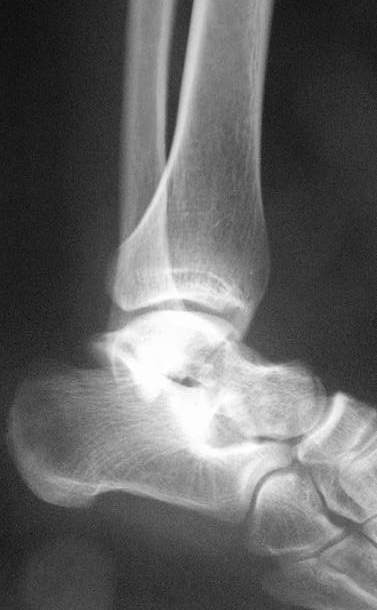

Прошу коллег помочь советом.3 дня назад поступила пациентка 23 года с переломом шейки ладьевидной справа, переломом лодыжек и заднего края б/берцовой кости со смещением и подвывихом кзади, переломом внутреннего мыщелка правого бедра без смещения. Дежурными хирургами проведена репозиция в левом г/ст суставе успешная, попытка репозиции таранной кости ухудшило положение отломков. Планируем провести повторную репозицию и фиксацию винтами. 1. Закрытая репозиция рентгенконтоль интраоперационный (аппарат Арман) ификсация из заднее-наружного доступа. 2. При неудачной закрытой репозиции переходим на открытое вправление двумя доступами медиальным и латеральным "по ходу оси таранной кости" и через дополнительный задний доступ вводим винты кортикальные 4,5 мм или 3,5 мм 3. после открытой репозиции фиксация двумя винтами через боковые доступы погружая их под суставную поверхность Сергей Зырянов ЦРБ Новосибирская область

Переломовывих тарана с повреждением медиальной стороны. Через 4 часа после поступления проведена репозиция и фиксация тарана после Irrigation&Debridment. Частичное несращение медиальной лодыжки не беспокоит, вернулся к активному образу жизни. Полная нагрузка разрешена через 11 недель. Финальные снимки через 11 месяцев.